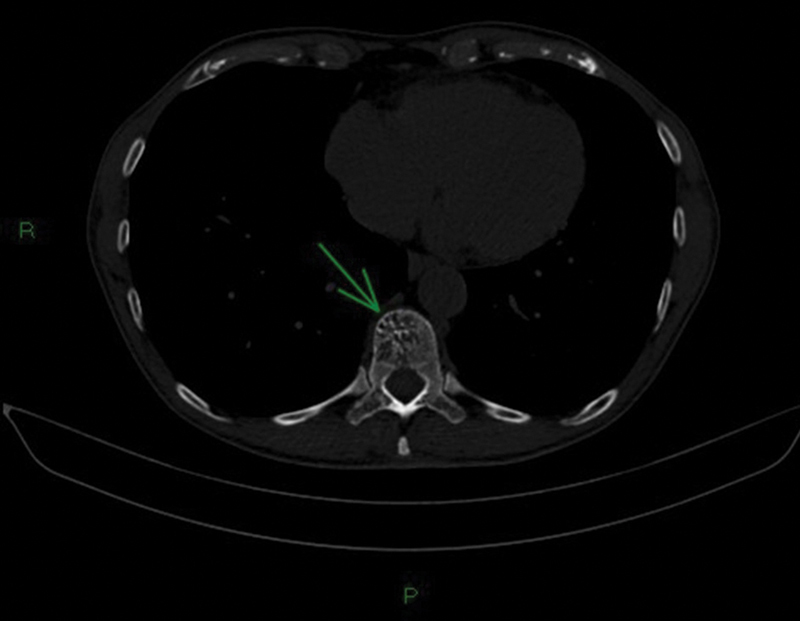

Collisions lesions are rare neoplasms where two histologically distinct tumors coexist in the same organ or anatomical site. Vertebral hemangiomas (VHs) are the most common lesions involving the vertebral bodies and imaging findings of typical and atypical hemangiomas, variant forms of hemangioma such as aggressive hemangiomas are well known, but collision lesions involving VHs are extremely rare. This article presents a case report of a 73-year-old male patient diagnosed with clear cell renal cancer in a rare presentation of a bone metastasis coinciding with the same anatomical position as a VH (collision lesion). This required a multidisciplinary approach involving various diagnostic techniques to determine the best therapeutic management.